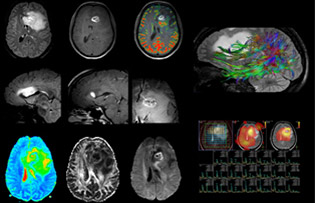

Dr. Savatovsky nutzt fünf oder sechs verschiedene ExamCards für die Bildgebung einer Raumforderung oder eines bekannten Tumors im Gehirn. „Wenn eine Raumforderung im Gehirn vorliegt, versuchen wir diese zu charakterisieren, um dem Neurologen die Informationen zur Festlegung des nächsten Schrittes zu liefern bzw. den Neurochirurgen bei der Vorbereitung eines Eingriffs oder einer Biopsie zu unterstützen. Für die Untersuchung nach einer Behandlung verfügen wir je nach Therapieform über verschiedene Protokolle und wir verfolgen spezifische Ansätze bei intra- und extraaxialen Tumoren.“ „Dies ist die umfassendste Untersuchung, die wir durchführen. Ingenia liefert aufgrund der guten räumlichen Auflösung und des hohen Signal-Rausch-Verhältnisses alle diese Daten. Außerdem ist das System so flexibel, dass damit kürzere Sequenzen möglich sind. Somit sind wir in der Lage, eine sehr umfangreiche Untersuchung in begrenzter Zeit vorzunehmen.“

„Die größte Herausforderung besteht in der sachgemäßen Charakterisierung der Läsion und der angemessenen Information des Chirurgen, zum Beispiel was die Position der Gefäße und der funktionellen Bereiche betrifft. Gelegentlich ist eine sehr umfassende Untersuchung notwendig, beispielsweise wenn eine Raumforderung an einem anderen Krankenhaus festgestellt wurde und der Patient anschließend an uns überwiesen wurde. Wir führen dann eine Charakterisierung der Läsion und eine präoperative Bildgebung in einer Untersuchung durch, d.h. sowohl eine morphologische als auch eine funktionelle Beurteilung. Für die morphologische Beurteilung verwenden wir eine T1-gewichtete Prä- und Postkontrastbildgebung sowie FLAIR für die Beurteilung der Infiltration und Diffusion. Für die funktionelle Charakterisierung führen wir eine Perfusionsbildgebung, eine MR-Spektroskopie und eine suszeptibilitätsgewichtete Bildgebung durch, um Mikrogefäße oder Mikroblutungen innerhalb der Läsion aufzuspüren[4]. Für die präoperative Untersuchung führen wir eine spezifische morphologische Bildgebung durch, die mit dem Navigationssystem kompatibel ist. Je nach Position des Tumors erfolgt fMRT oder TDI.“